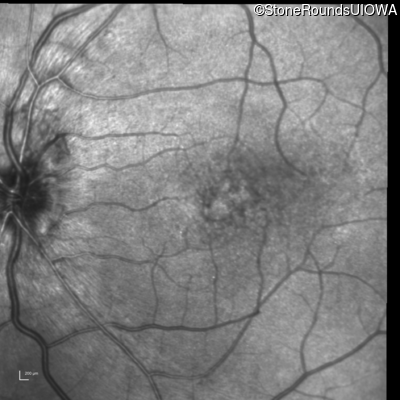

Visit at age: 16 years

Fundus Photography - Left - 20/50 -3

Exemplar